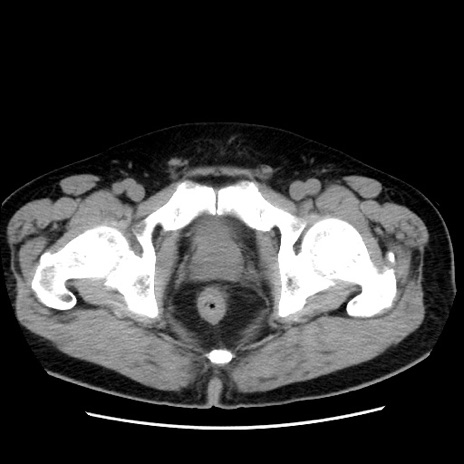

症例16(横断像)

【症例】 70歳代男性

【主訴】 腹痛、嘔吐

【現病歴】 約1ヶ月前より間欠的に腹痛と嘔吐あり、当院消化器内科を受診したところCTで多発する肝臓のLDAを指摘され、精査中であった。以降は消化器症状は安定していたが、2日前より嘔気と腹痛があり、同日より排便・排ガスが消失した。改善認めず、 本日、救急外来を受診した。

【既往歴】 大腸ポリープ切除後。

【身体所見】意識清明・会話良好、BT 36.3℃、BP 127/80mmHg、 P 80bpm、腹部:膨満あり、平坦・軟、上腹部正中および下腹部正中に圧痛あり、反跳痛なし、筋性防御なし。

【データ】WBC 7200、CRP 0.77